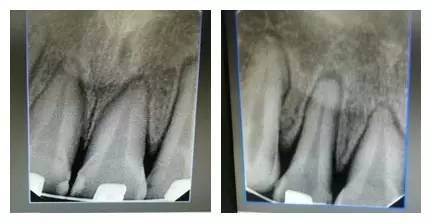

由上圖可知,患者全口牙齒磨耗較重,尖牙牙尖磨耗,無(wú)法起到引導(dǎo)和保護(hù)作用,上前牙牙根短,上中切牙腭側(cè)面邊緣嵴消失,

由此推斷:尖牙牙尖磨耗,患者在前伸(牙合)運(yùn)動(dòng)時(shí),引導(dǎo)不足,前牙的接觸面過(guò)大,受力較大;患者在側(cè)方(牙合)運(yùn)動(dòng)時(shí)下前牙沒(méi)有了引導(dǎo),會(huì)直接對(duì)側(cè)切牙造成撞擊;再加上前牙根較短,無(wú)法耐受,引起(牙合)創(chuàng)傷,繼發(fā)牙髓癥狀;失去尖牙保護(hù)(牙合),加重了牙齒的磨耗。